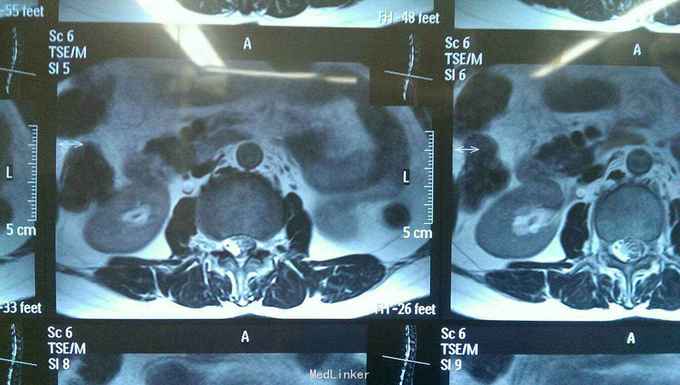

神志清楚,语言流利。颅神经检查未见异常。右侧臀部一下浅深感觉减退,肌力四级。生理反射存在,病理反射未引出。括约肌功能正常。核磁共振提示腰1--3椎管内多发病变,明显强化。

入院诊断椎管内多发占位病变,神经纤维瘤。完善术前准备后行后正中入路神经纤维瘤切除术。术中见马尾神经生长多个肿瘤,与其余神经无粘连,完整切除肿瘤。

术后患者无新增神经功能障碍,感觉麻木略有好转。多发神经纤维瘤在椎管内比较少见,术前定位关键,由于马尾神经控制括约肌功能,术中操作一定轻柔。